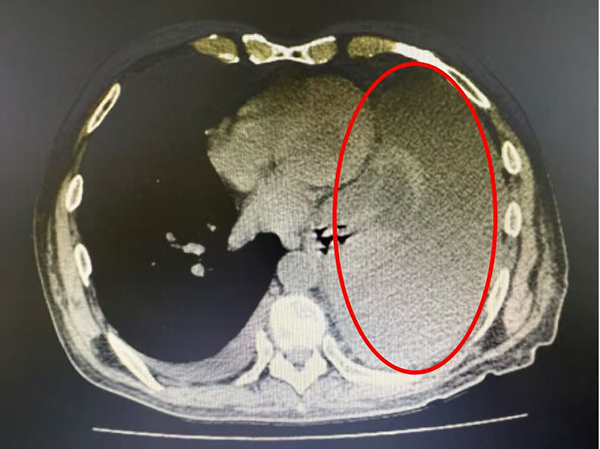

11天后,李先生顺利出院。出院1个月后复诊,双肺CT显示左侧胸水无增多,“现在我能平躺着睡整夜觉了,这种久违的自由呼吸,就像重新找到了生命的锚点。”李先生动情地说。出院3个月后的回访,更是传来了喜人的消息,李先生的胸水依旧没有增多。“通过复查、回访,我们的治疗应该可以维持一个长期的疗效。”曲博主任兴奋地说道。

图片2.png

出院后复查双肺CT